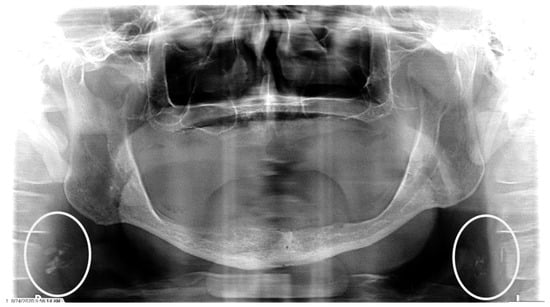

Figure 1.

The panoramic radiograph of a 67-year-old male patient with a medical history of hypertension, diabetes mellitus, and coronary artery disease showing a unilateral right carotid artery calcification (CAC) during a comprehensive dental examination. The CAC is encircled by a white line.